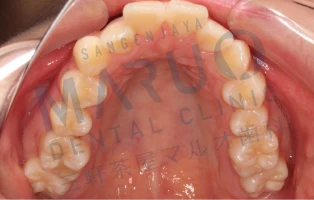

06.三軒茶屋マルオ歯科矯正担当医の治療例

症例1

治療前

治療中

動的治療終了時

| 主訴 | 上の前歯が前に出ている 歯のでこぼこ |

|---|---|

| 診断名 | 上顎前突 叢生 |

| 年齢 | 13歳 |

| 治療に用いた主な装置 | マルチブラケット装置 |

| 抜歯部位 | 上下両側第一小臼歯 |

| 治療期間 | 2年6ヶ月 |

| 治療費 | 92万4,000円(税込) |

| リスク、副作用 | むし歯や歯周病、歯根吸収、治療後の後戻りの可能性があります |